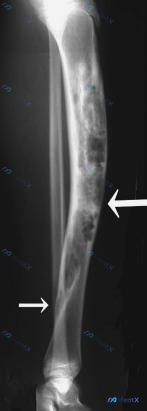

病例资料整理 患者信息:女性,21 岁。 主诉:腿部疼痛和畸形持续 7 年。 现病史:14 岁时发现异常,至今病程 7 年。 影像学检查: 1. X 光(14 岁及当前):胫骨骨干大范围溶骨性骨质破坏,呈膨胀性改变,骨皮质变薄,内部可见骨纹理消失及残留骨嵴(多房样改变)。侧位片可见胫骨前侧软组织轮廓...